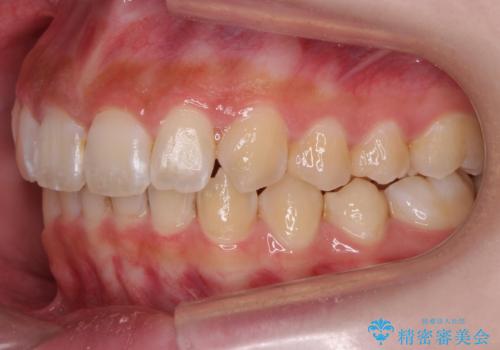

前歯の並び インビザライン 非抜歯で 深いかみ合わせの治療

- 前歯の並びを気にして来院。

上の前歯が内側に倒れこんでいました。

インビザラインで前歯の並びを整えています。

前歯の重なりが大きいいわゆる過蓋咬合を呈していましたが、ある程度適正な重なりにすることができました。